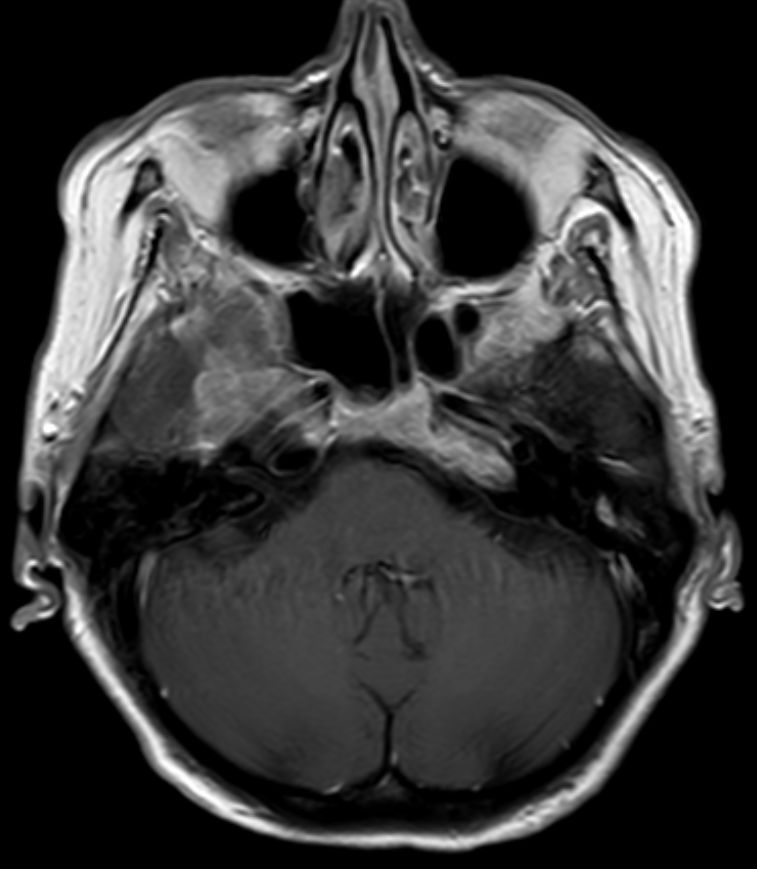

| Schädelbasis | 62-jährige Frau, bei der vor 2 Monaten ein Plattenepithelkarzinom der Zervix FIGO IIIB mit Radiochemotherapie behandelt wurde. Die Uterusgröße hatte von 13 auf 6 cm abgenommen. Jetzt Aufnahme mit der Diagnose Apoplex. | |||

An der Basalfläche des rechten Temporallappens KM - aufnehmende RF.![]() |

![]() | |||

![]() |

Unklare Doppelkontur der Meningen des Halsmarks.![]() |

Ödem des rechten Temporallappens.![]() | |||